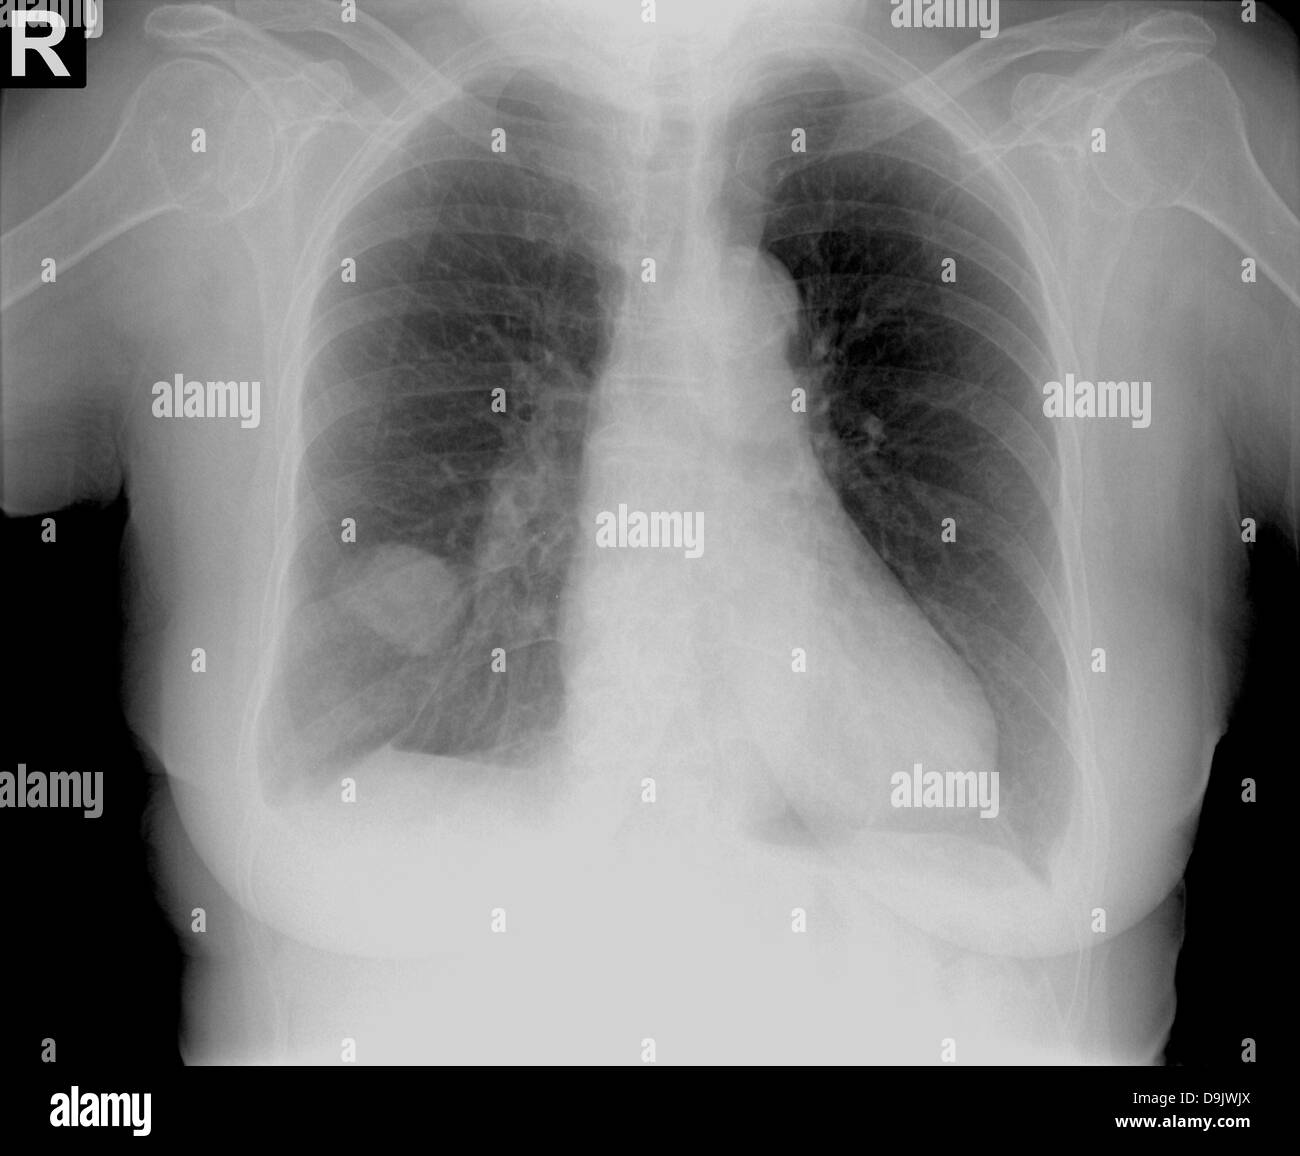

Radiographie thoracique ou radiographie du thorax humain pour un Radio Thorax Slideshare Normal radiographic anatomy of the thorax • obtaining a good thoracic radiograph • review anatomy • case examples obtaining a good thoracic radiograph • good quality image improves. Radiological anatomy of the chest. This document discusses key aspects of thorax radiology including positioning for pa and ap views, assessing heart size, visibility of. Radiological anatomy of thorax dr. • with. Radio Thorax Slideshare.